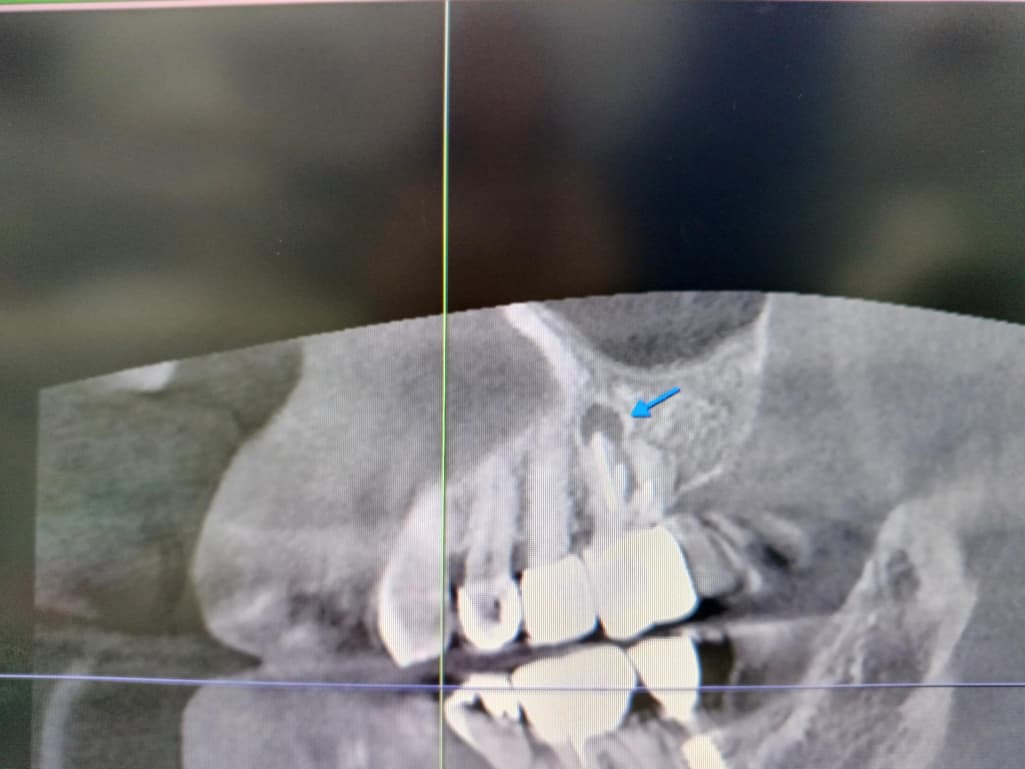

신경치료 후 크라운 장착한 치아뿌리 염증상태 입니다 잠잘때는 통증이 거의 없는데 일어나서 일상 중 통증이 있으며 말을할때 더 아픕니다 염증이 크기가 저정도면 큰편인지 저정도면 발치해야 되는지

저 치아가 옆주변 치아에도 영향을 주는지 문의드립니다

옆치아에 영향을 줄 수 있으며 염증이 큰 편이기때문에, 발치를 하셔야 할 것으로 보입니다.

사진으로봤을 경우에는 치근단에 병소가 생긴것으로 보입니다.

근단부위의 염증은 신경관의 감염으로 생기기 때문에 재신경치료를 해주는것이 좋을수 있습니다 .